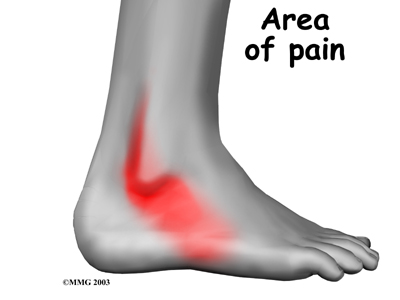

Patients describe a popping or snapping sensation on the outer edge of the ankle. The tendons may even be seen to slip out of place along the lower tip of the fibula. It is common to feel pain and tenderness . There may also be swelling just behind the bottom edge of the fibula.